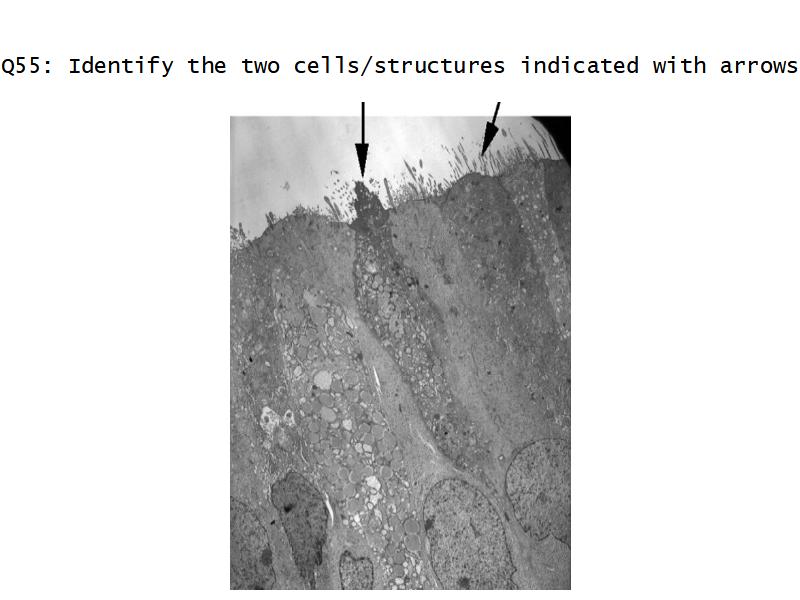

Respiratory epithelium

- Pseudostratified

- Ciliated

- Columnar

- Epithelium with

- 4 Cells

- Ciliated columnar cells

- Non-ciliated columnar cells

- Goblet cells

- Basal cells